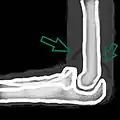

| A traumatic right knee effusion. Note the swelling lateral to the kneecap as marked by the arrow. | |